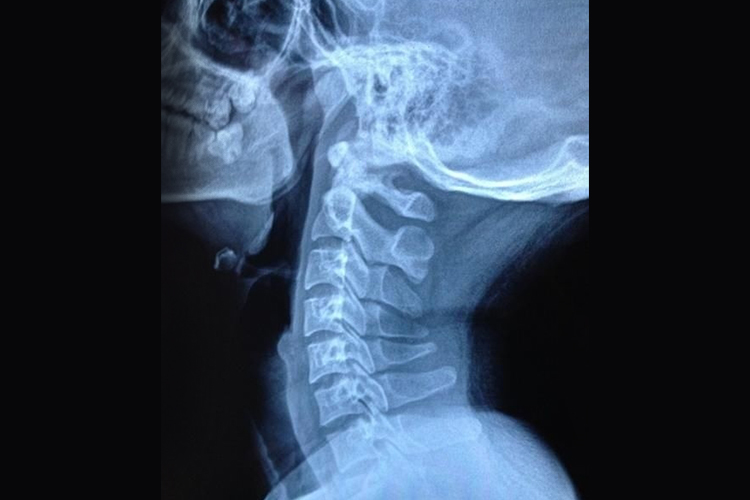

项韧带钙化是颈椎退行性变过程中的一种病理现象,指的是项韧带内钙质异常沉积,导致韧带硬化、弹性降低,进而影响颈椎的稳定性与活动度,由多种因素共同作用而成,还应及时进行处理。